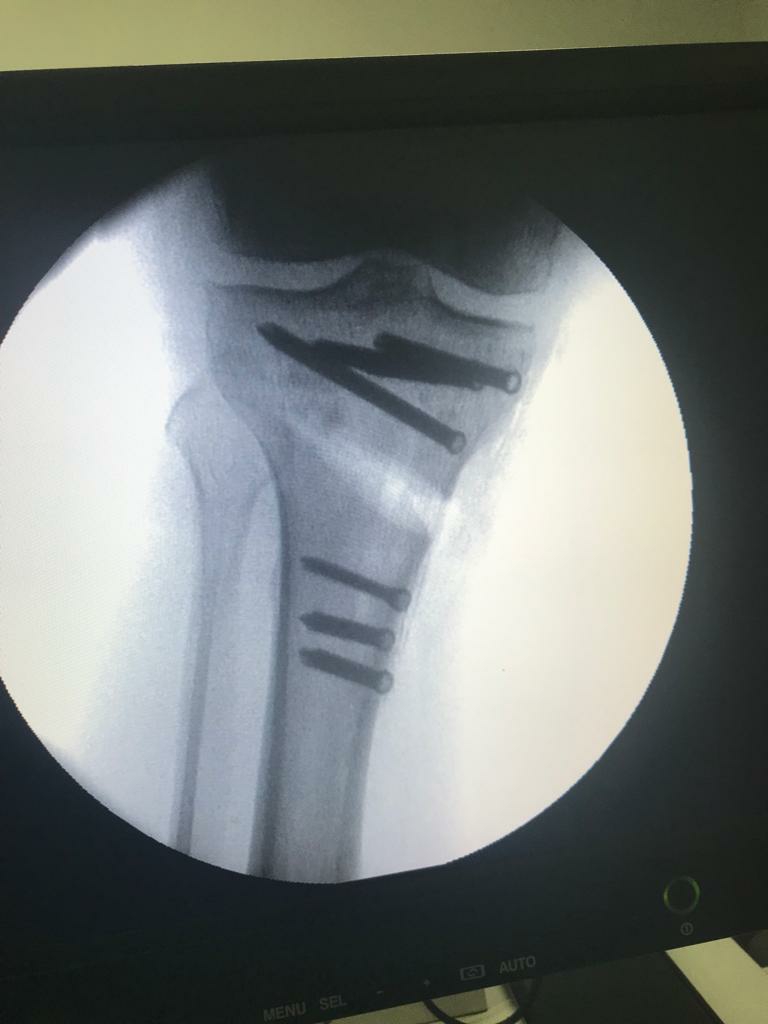

HTO for Arthritis Using PEEK Plate